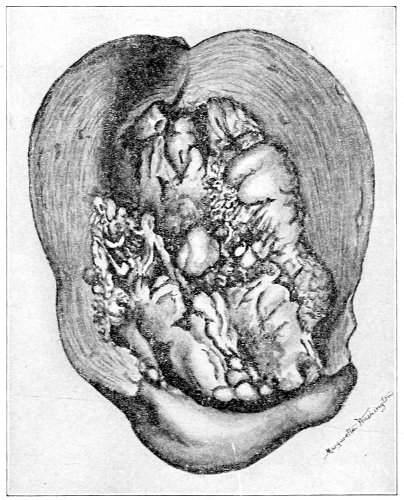

Cysts of the gland may be unilocular if formed at the expense of a single lobule of the gland, or multilocular if several lobules enter into their formation. These cysts may attain the size of the fetal head (Fig. 18).

These cysts contain clear yellow or chocolate-colored 42 fluid. The diagnosis of cyst of the vulvo-vaginal gland is usually not difficult. If we are in doubt in regard to the fluid character of the tumor, this may be determined with the exploring-needle.